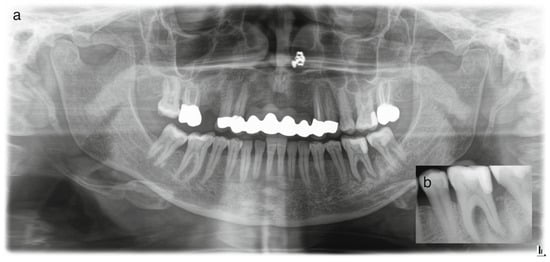

Objective: To report a rare case of pulp space tissue growth in a mature mandibular molar with severe endo-periodontal involvement after conservative endodontic treatment and to discuss the possible biological explanations, including regeneration and granulation tissue healing. Severe endo-periodontal lesions are challenging, particularly [...] Read more.

Objective: To report a rare case of pulp space tissue growth in a mature mandibular molar with severe endo-periodontal involvement after conservative endodontic treatment and to discuss the possible biological explanations, including regeneration and granulation tissue healing. Severe endo-periodontal lesions are challenging, particularly as endodontic regeneration is usually observed in immature teeth, while revascularization in mature teeth, especially in cases of advanced periodontal disease, is rare, as demonstrated in this case. Methods: This study reports a rare case of tissue regeneration versus granulation tissue healing in the pulp space, occurring alongside periodontal healing, in a mature mandibular molar with necrotic pulp and severe periodontal involvement. A 52-year-old patient presented with a mature mandibular molar (tooth #19) exhibiting necrotic pulp with severe endo-periodontal involvement, including grade-3 mobility, tenderness to percussion, a 12 mm probing depth, and extensive periradicular radiolucency. The tooth was diagnosed with necrotic pulp and symptomatic apical periodontitis and was deemed hopeless, with extraction planned. Results: Following patient refusal, endodontic treatment was initiated, including cleaning, shaping, and placement of the intracanal medicament, Ledermix. The patient canceled the extraction due to symptom resolution and disappeared for 12 months. On return, the patient presented with spontaneous pain exacerbated by thermal stimuli, consistent with symptoms of irreversible pulpitis. Clinical examination revealed significant clinical and radiographic improvements, including reduced probing depth (3 mm), no mobility, resolution of apical translucency, radiographic findings suggestive of canal narrowing, and a positive pulp sensibility response. Re-entry elicited profuse bleeding with newly formed vital tissue beneath the medicament. Sodium hypochlorite irrigation failed to achieve hemostasis; inflamed tissue was removed; root canals were cleaned, shaped and obturated; and treatment was completed with placement of a permanent coronal resin composite restoration. A forty-month follow-up showed an asymptomatic tooth with clinical and radiographic healing. Conclusions: This case demonstrates that conservative endodontic management may result in favorable clinical and radiographic outcomes in mature teeth with severe endo-peroidontal involvement, influencing extraction decisions. It provides clinical evidence suggestive of tissue regeneration and periodontal healing in a mature tooth with necrotic pulp and severe periodontal compromise, challenging conventional prognosis. The observed pulp space tissue growth may be suggestive of regeneration; however, alternative explanations, including granulation tissue healing or repair processes, cannot be excluded. Healing by granulation tissue in the pulp space remains possible. Root canal treatment in advanced endo-perio lesions can yield favorable outcomes and may influence extraction decisions. Further clinical and histological studies are needed to clarify underlying mechanisms and optimize treatment strategies. Full article

Show Figures

Figure 1